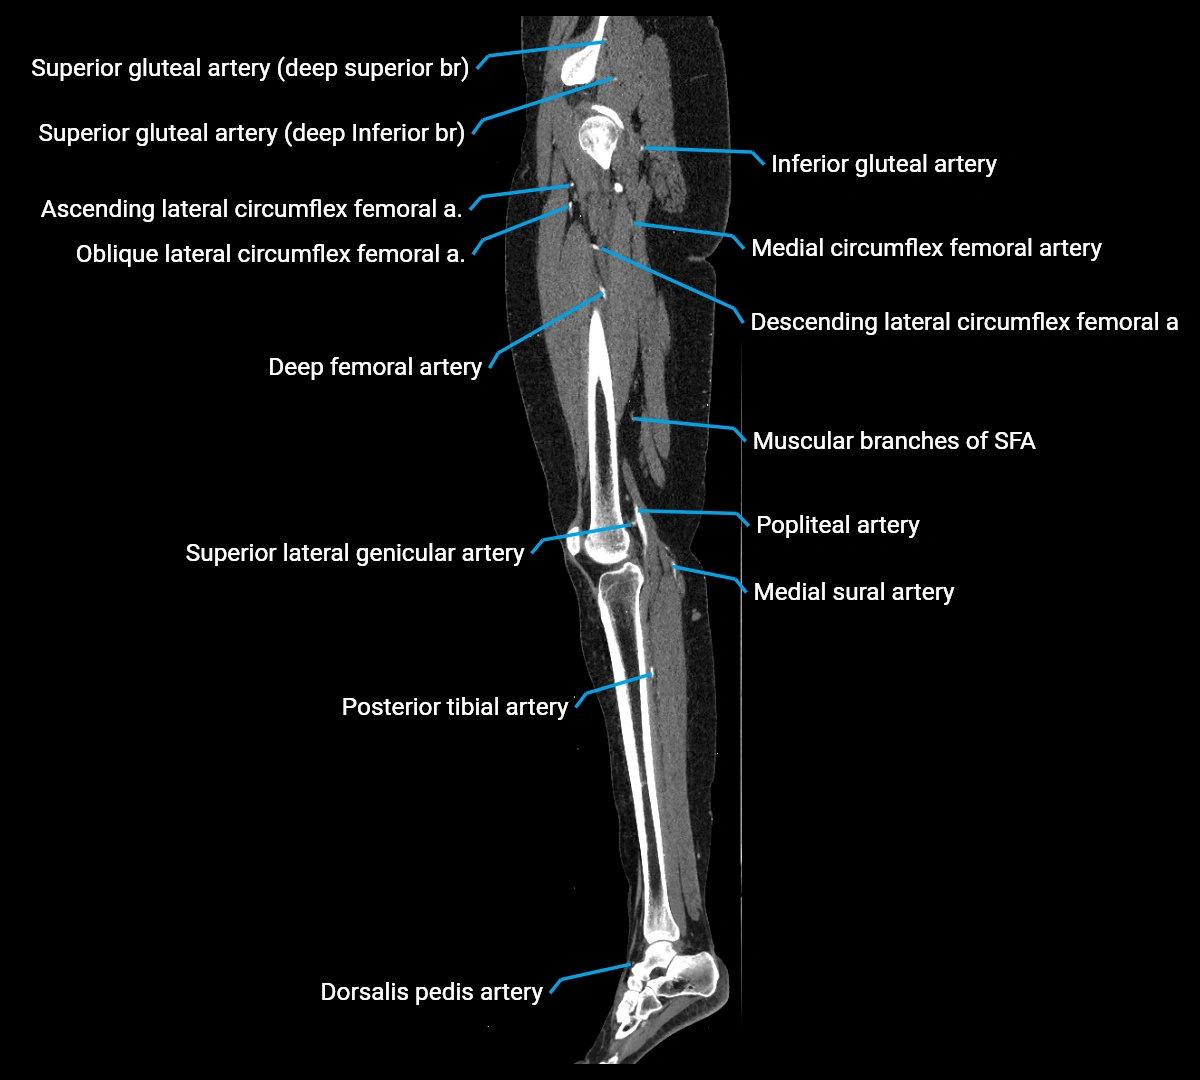

CT Appearance

Non-contrast CT:

• Appears as a tubular soft tissue structure anterior to vertebral bodies

• Calcified atherosclerotic plaques appear as hyperdense foci along the wall

• Useful for screening abdominal aortic aneurysm (AAA) size and mural calcification

Contrast-enhanced CT (CTA):

• Gold standard for abdominal aortic imaging

• Provides excellent detail of lumen, wall, aneurysm, thrombus, and branch vessels

• Multiplanar and 3D reconstructions help in aneurysm measurement, stent graft planning, and dissection evaluation

• Detects acute rupture, traumatic injury, or occlusion with high sensitivity